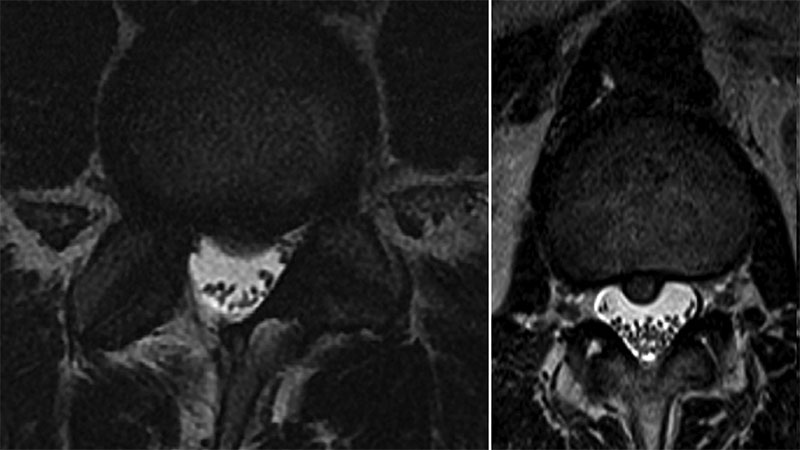

In a recent multicenter study, Nadeen O. Chahine, PhD, Associate Professor of Biomechanics (in Orthopedic Surgery), Columbia University Vagelos College of Physicians and Surgeons, showed, for the first time, that degree of inflammation is correlated with severity of disc herniation as measured on MRI – a gold standard for herniation diagnosis. The researchers also found that this relationship holds only in patients with chronic symptoms, suggesting that the inflammation is developing over the longer course of herniation. To determine how intervertebral disc disease and subject-specific characteristics contribute to lower back pain, the researchers examined the effects of symptomatic disc herniation and MRI herniation severity on serum cytokine levels in patients. The study provided a better understanding of the inflammatory proteins contributing to pain and disability and the opportunity to develop new therapies for patients with recurring symptoms or who are not candidates for surgery.

MRI images showing two levels of disc disease severity